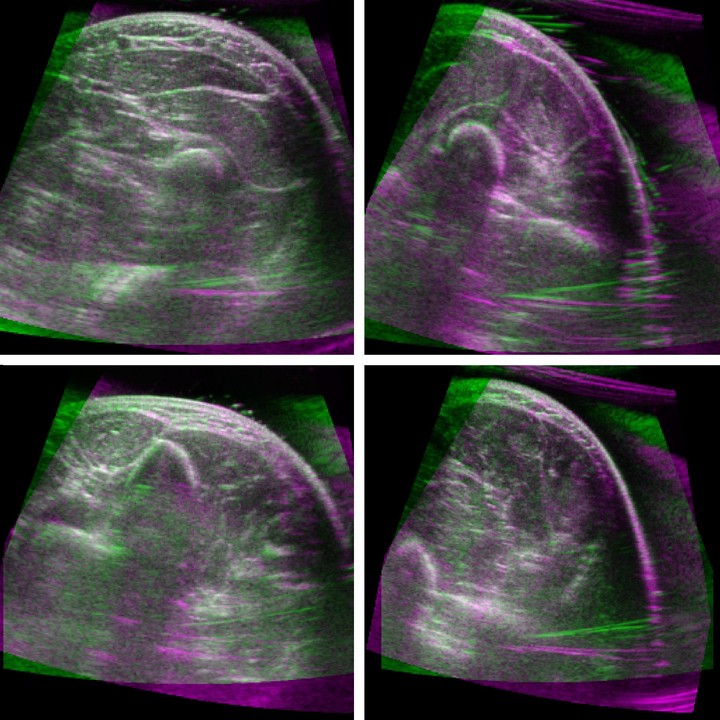

Statistical consensus matching framework for image registration

A common method for image alignment in computer vision is finding the maximum consensus transformation for a set of features in the …